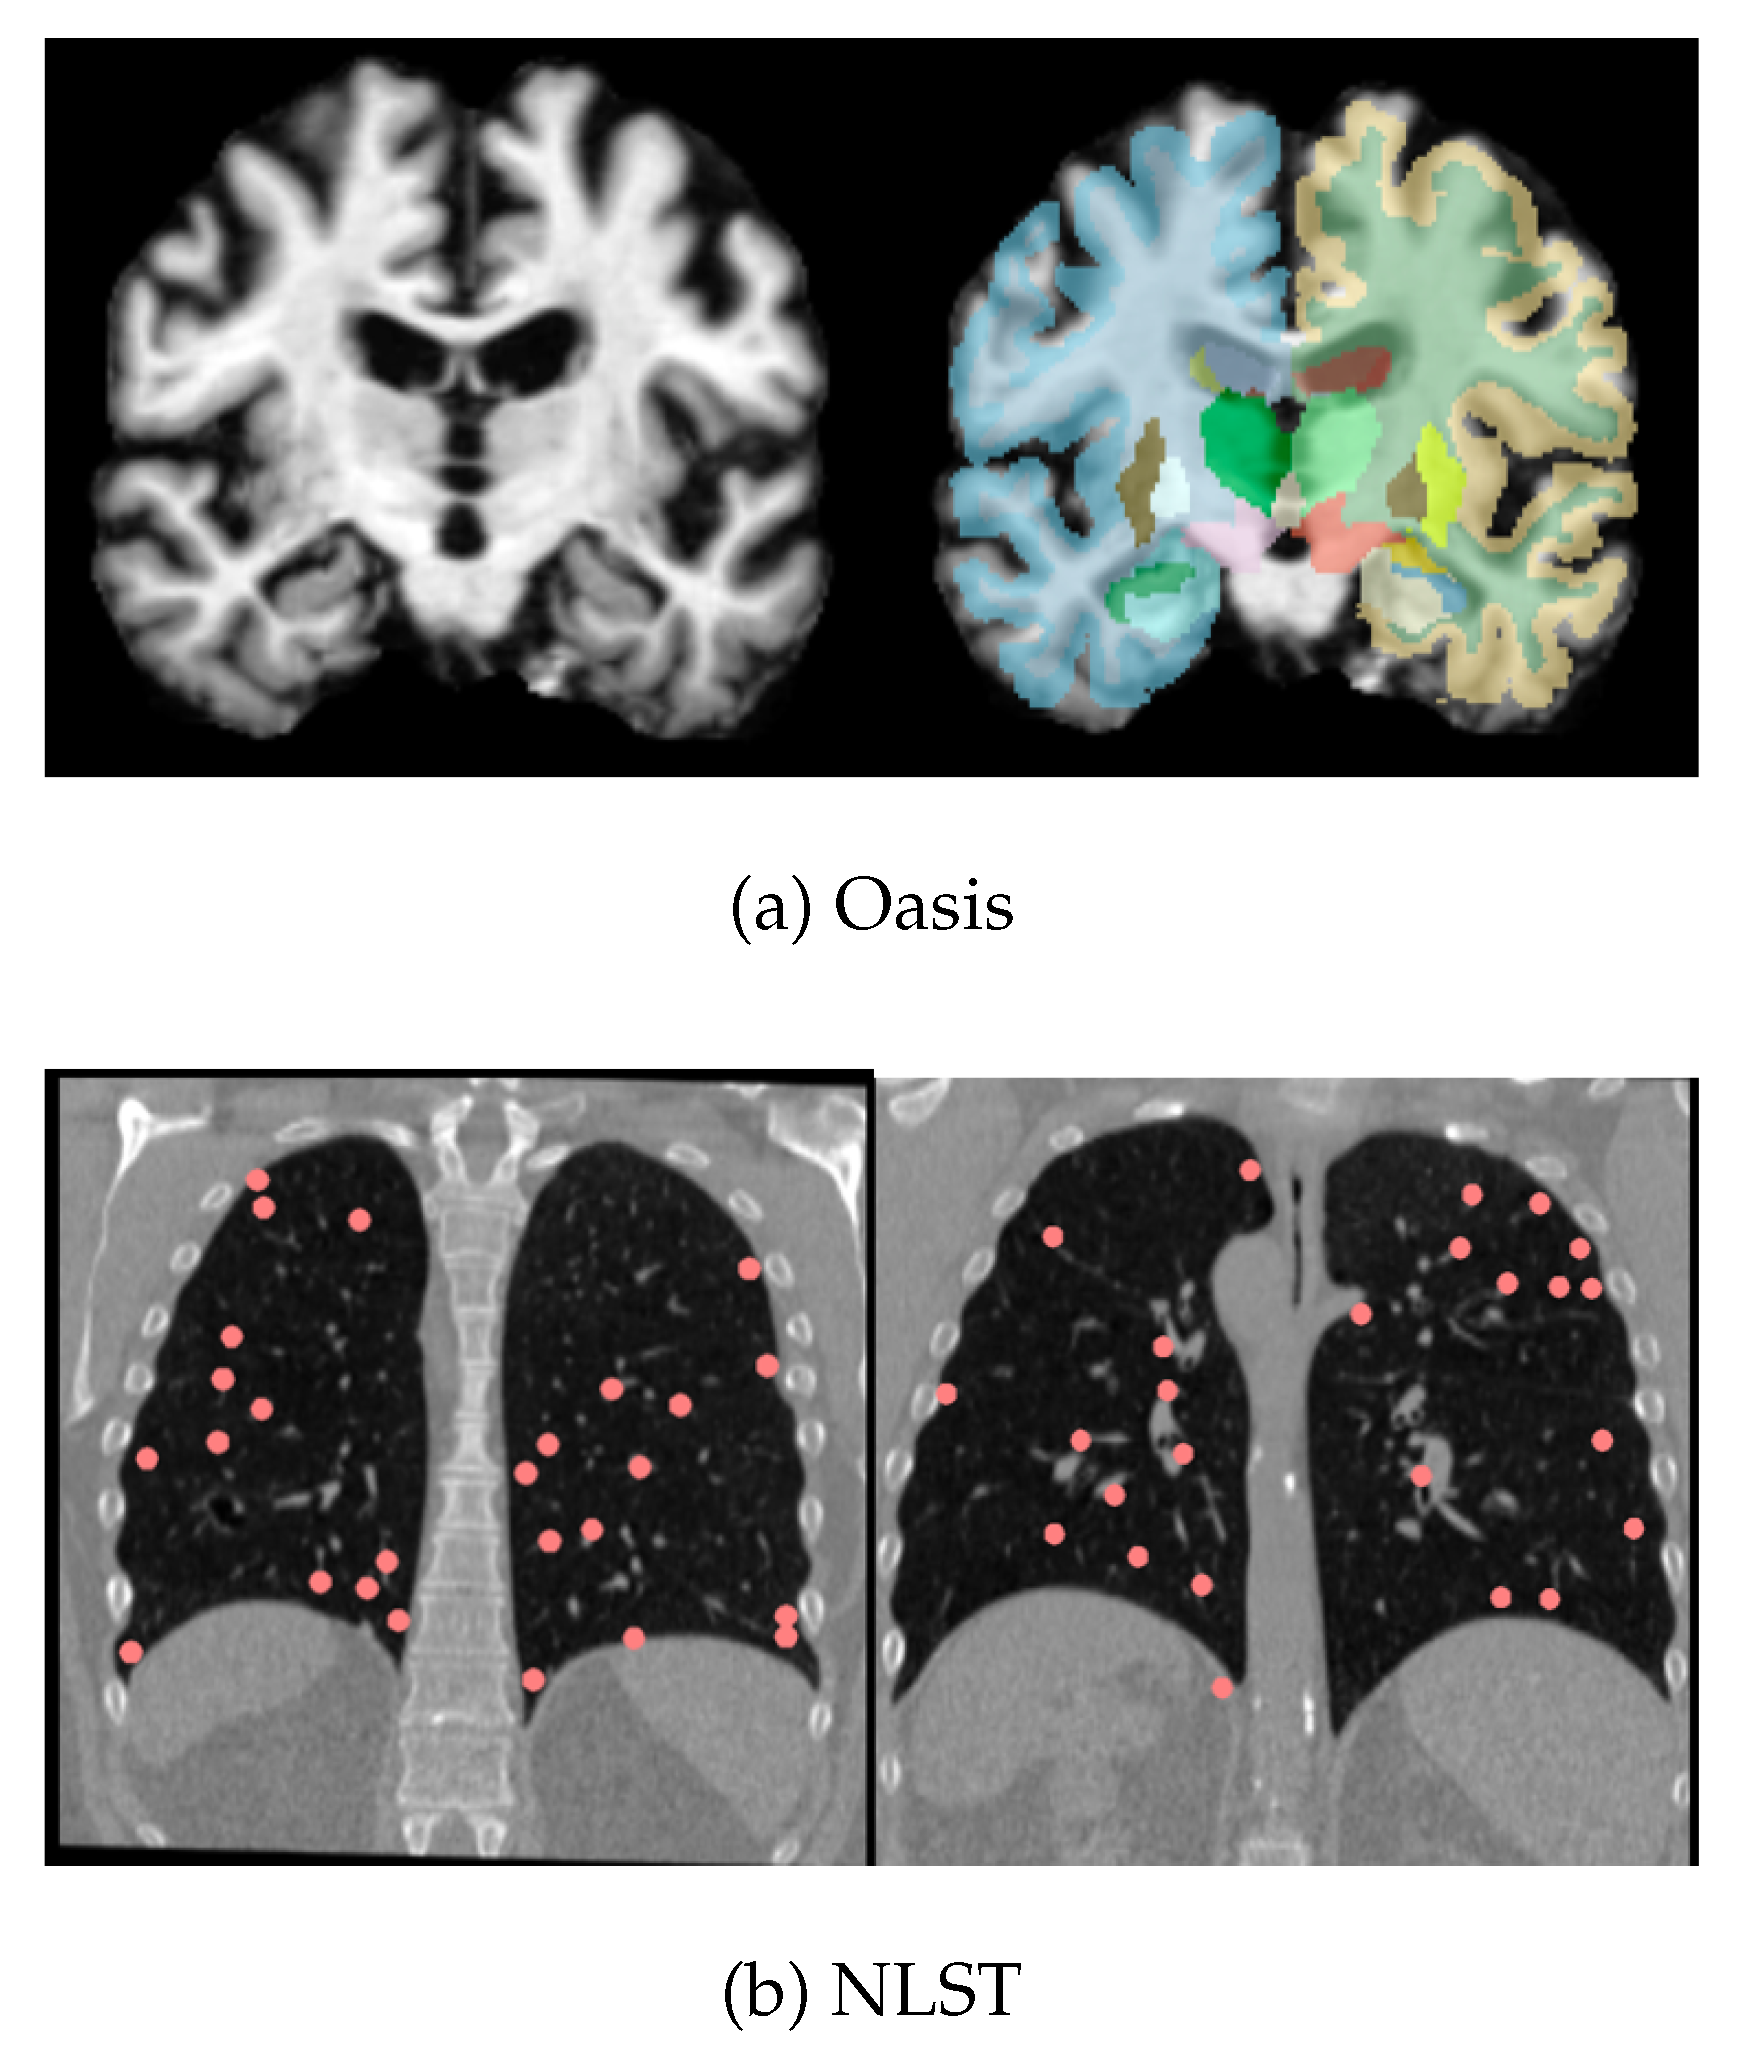

Experiments were performed with the OASIS [20] and NLST [21] datasets prepared for the MICCAI 2022 Learn2Reg workshop challenge [22] (Figure 3). The OASIS dataset consists of 414 T1-weighted MRI scans of individuals from ages 18-96 with mild to severe Alzheimer’s. The scans are skull-stripped and resampled onto an isotropic grid and cropped to a uniform size. 35 segmentation labels are provided for important brain regions. The dataset is split into 395 images for training and 19 for validation. Intersubject registration in this context could be used for constructing a sub-population brain atlas or for analysing intensity changes in consistent brain regions that are linked to disease progression.

NLST is a lung-CT dataset with pairs of inhale/exhale scans; keypoints and masks are provided by the Learn2Reg challenge for semi-supervised training. We used a subset of the image pairs (100 out of 150) of the NLST dataset released by the Learn2Reg challenge for training and validation, with a 90:10 training/validation split. Since respiration is accompanied by a large change in lung volume, the displacement field required to register NLST is large, relative to OASIS.

Figure 3. Sample images from the OASIS (a) and NLST (b) datasets. Note, segmentations are available for the OASIS dataset and keypoints indicating the positions of nodules are available for the NLST dataset.